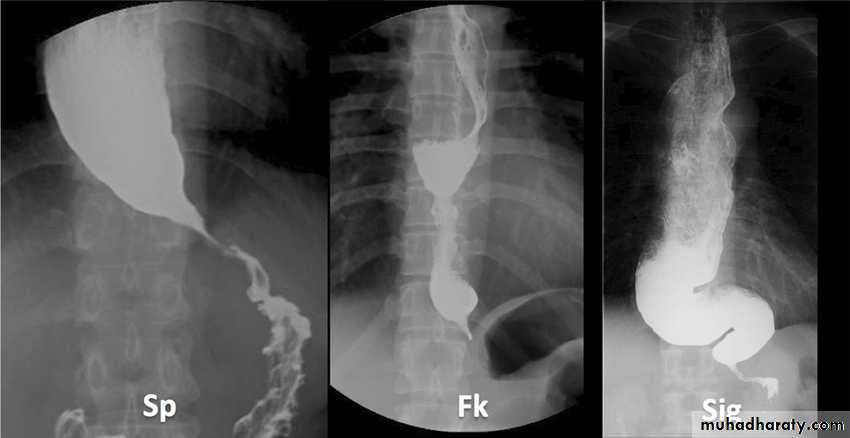

Chest x-ray may be abnormal in late dis., with widening of mediastinum (oesophageal dilatation) and presence of aspiration pneumonitis.Barium swallows . Tapered narrowing (bird beak) of the lower oesophagus and dilating body of oesophagus, a peristaltic and food filled (sigmoid oesophagus).